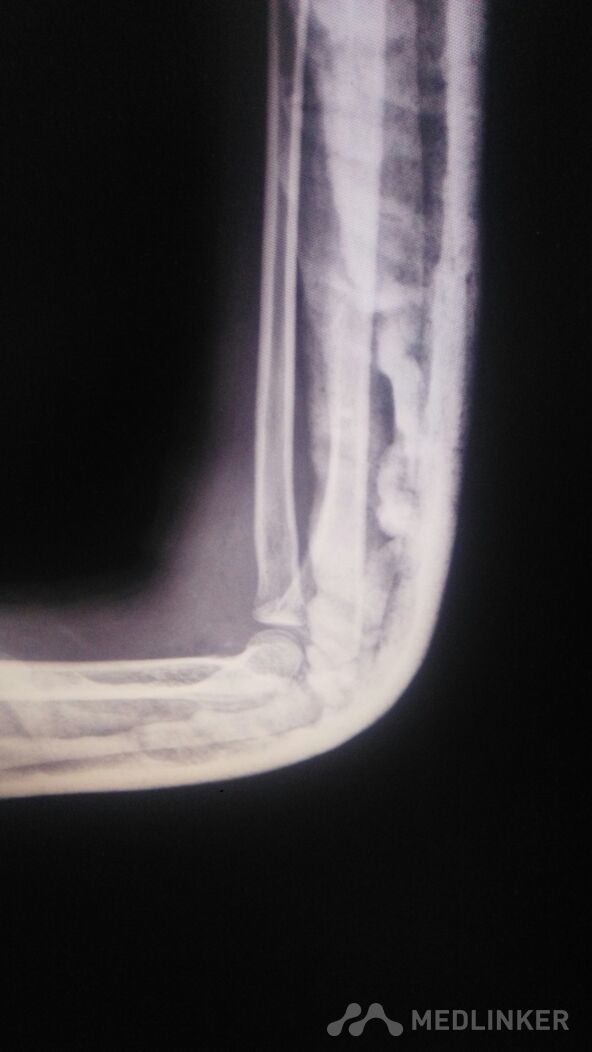

外伤后儿童的肘关节脱位。

左肘部肿痛畸形。以尺骨鹰嘴处为著,压痛阳性,叩痛阳性。左肘部活动受限。

骑自行车时摔倒致左肘部肿痛1小时。左肘部肿痛,畸形。活动受限。左手麻木。

左肘部脱位,后脱位,可以保守治疗。

肘关节肿胀明显。畸形明显。虽然脱位,韧带也有损伤。恢复有一定的时间。